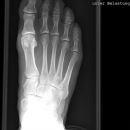

Fuß dorso-plantar (a.-p.) 1. Ebene

Technik

• FDA: 1,05 m

• Ausgangsformat: 24/30

• Übertischaufnahme

Indikation

Fraktur, entzündliche und degenerative Veränderungen

Lagerung

sitzend/ liegend auf Tisch

Knie gebeugt und Fuß aufgestellt

Fußsohle liegt plan auf Bildempfänger

Zentralstrahl

senkrecht auf Objektmitte

Einblendung

proximal bis einschließlich Malleolus lateralis

Qualitätskriterien

Möglichst überlagerungsfreie Aufnahme der Mittelfußknochen, sodass die Fußwurzel-Mittelfuß- Gelenke gut beurteilbar sind.